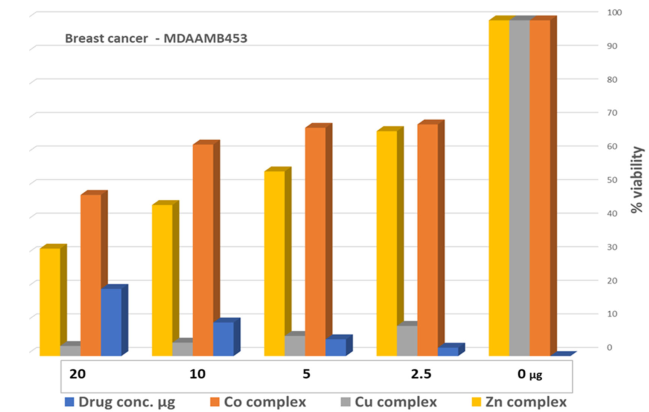

2.9. Cell Proliferation Assessments

| Parameter | Dilution Used to Treat the Cells with the Metal Complexes/µg | ||||

|---|---|---|---|---|---|

| |||||

| Co–ligand complex 1:1 |   | ||||

| Drug conc µg | 0 | 2.5 | 5 | 10 | 20 |

| Mean—blank | 100 | 69.2 | 68.4 | 63.6 | 48.1 |

| Standard deviation | 8.00 | 7.15 | 7.08 | 8.29 | 3.07 |

| HEK293 | - | - | - | - | 80.50 ± 3.139 |

| Cu–ligand complex 1:1 |   | ||||

| Drug conc µg | 0 | 2.5 | 5 | 10 | 20 |

| Mean—blank | 100 | 9.80 | 6.06 | 3.91 | 3.31 |

| Standard deviation | 7.97 | 1.58 | 0.34 | 0.44 | 0.34 |

| HEK293 | - | - | - | - | 66.66 ± 4.586 |

| Zn–ligand complex 2:1 |   | ||||

| Drug conc µg | 0 | 2.5 | 5 | 10 | 20 |

| Mean—blank | 100 | 67.1 | 55.7 | 45.2 | 32.1 |

| Standard deviation | 2.45 | 0.92 | 6.14 | 3.17 | 4.80 |

| HEK293 | - | - | - | - | 67.77 ± 5.875 |